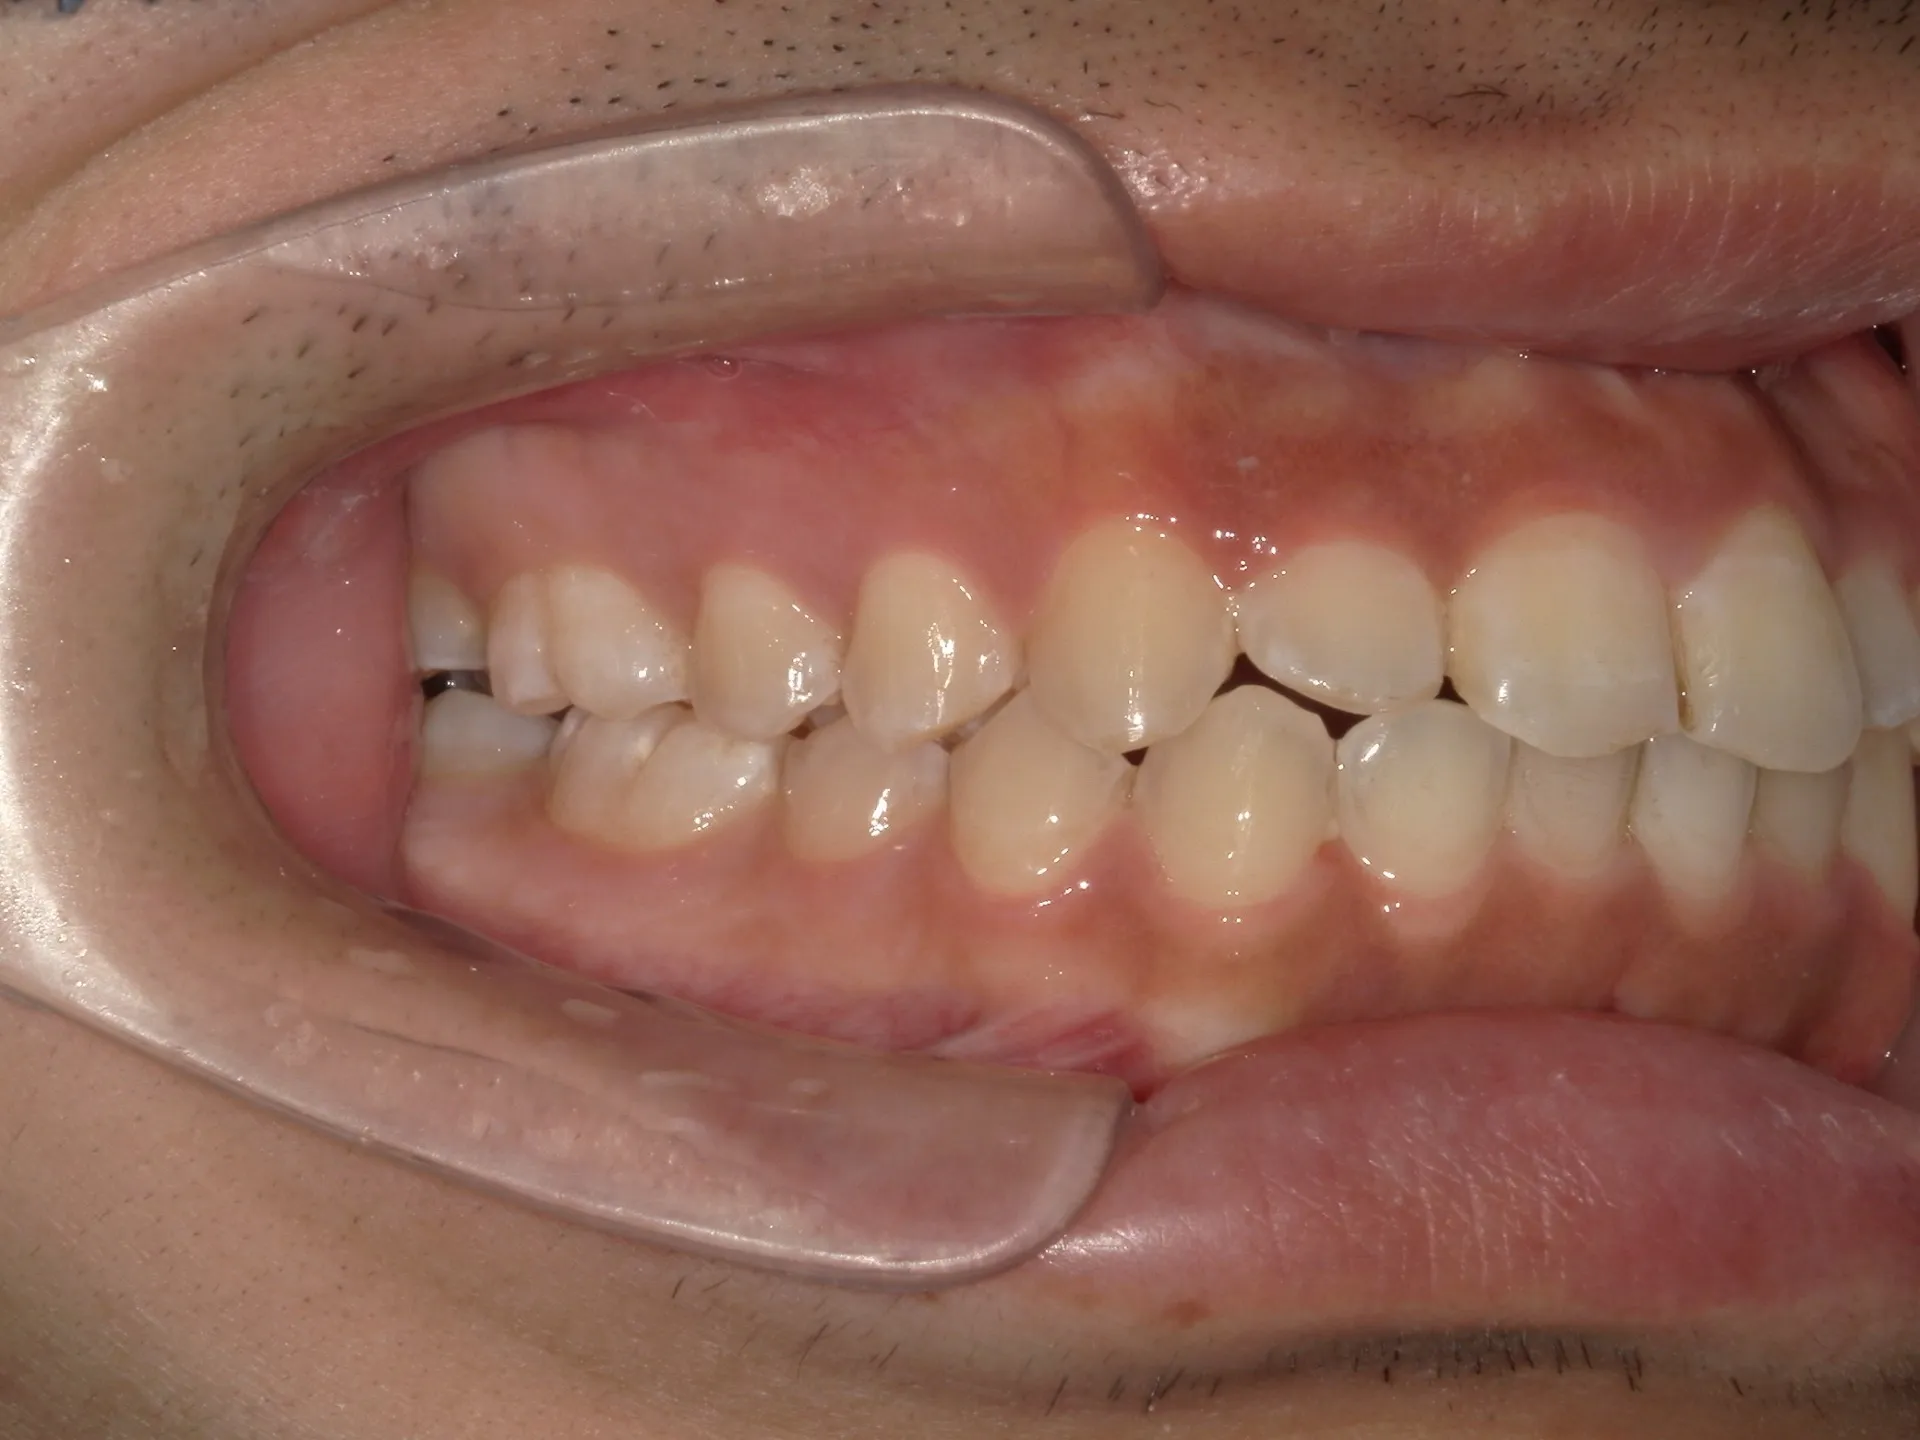

今回は他院さんでインビザライン矯正治療を受けていた患者様を引き継いで当院でインビザライン治療を継続した症例をご紹介致します。

今回はマウスピース矯正を主軸にした矯正ですが、一部ワイヤー矯正も併用して改善しております。